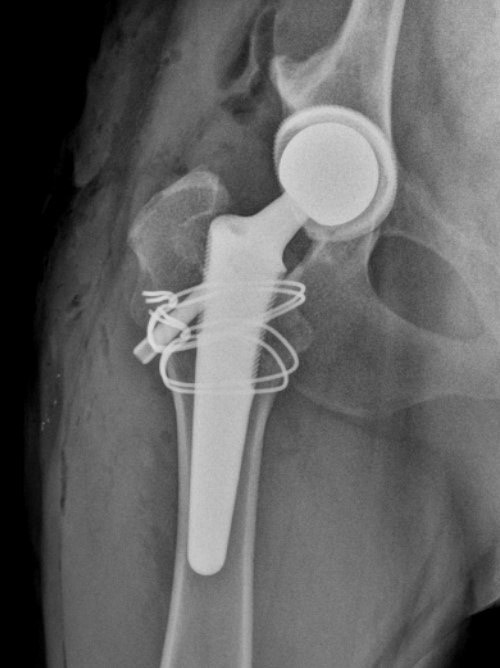

Image 2: An intra-operative fissure occurred while preparing the femur for an uncemented femoral stem. Two double loop cerclage were placed and a BFX Lateral bolt stem place